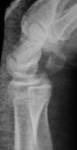

От хирурга.

200907290019.jpg200907290021.jpg200907290025.jpg200907290027.jpg

После наложения гипса.

200907290031.jpg200907290032.jpg200907290034.jpg200907290035.jpg